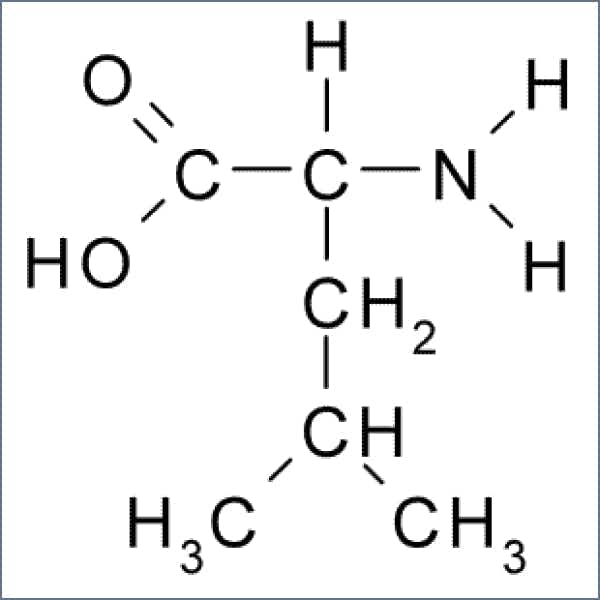

L-Leucine#

Leucine must be present for optimal metabolic functions, including muscle and bone growth and repair. Your body’s growth hormone synthesis depends upon leucine for blood sugar regulation. This amino acid is also important for wound healing and prevents the muscle protein breakdown that occurs after intense workouts.2

L-Valine #

Valine is closely related to Leucine and also helps promote muscle growth and repair. The amino acid helps with your muscle coordination, mental vigor, and emotional stability. People need Valine for optimal physical and mental energy.3

L-Isoleucine#

Isoleucine is a detoxifier. It detoxifies nitrogenous waste, aids in wound healing, and helps your body release beneficial hormones. You need this amino acid in order to produce hemoglobin, which improves athletic performance and immune function. It also plays a key role in regulating the body’s blood sugar levels, which keeps your energy balanced.4

L-Lysine HCL#

Lysine is essential for tissue growth and repair. In supplement form, L-lysine helps your body absorb calcium and improves immune function. You need this amino acid for optimal production of collagen, which keeps your connective tissues healthy and helps heal wounds.5

L-Phenylalanine#

Phenylalanine is an amino acid that’s essential for synthesizing dopamine, tyrosine, and norepinephrine—three neurotransmitters that control key brain functions. These brain functions influence your vigilance, action, memory, learning, and reward pathways—all tools you’ll need for optimal athletic performance.6

L-Threonine#

Threonine is an important contributor to structural proteins such as collagen, elastin, and tooth enamel. It helps with your body’s fat metabolism and immune system function. The amino acid keeps fat from building up in the liver as well. In supplement form, it’s known to improve digestion and mood, and alleviate mild anxiety and depression.7

L-Methionine#

Methionine is important for the repair and growth of tissue. It strengthens your hair, skin, and nails. It’s an important detoxifier and assists in the excretion of heavy metals like lead and mercury. Methionine protects your cells from aging and prevents fat from accumulating in your liver.8

L-Tryptophan#

Tryptophan is known as a natural sedative but is also a precursor to serotonin. It’s essential for our feelings of contentment. It also helps regulate appetite, mood, sleep, and our response to pain.9